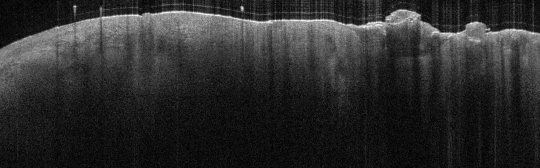

VA28: Right Lateral Arm, Squamous Cell Carcinoma, Invasive

- Arrows denote lower margin of squamous mass, note indistinct boundary and merging with collagenous dermis texture

VA28: Left Lateral Arm, Contra Lateral, Normal